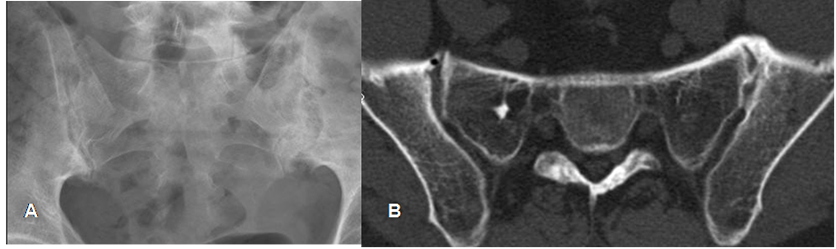

Fig 7. Sacroileitis.

A: Rx AP. Cambios crónicos en ambas SI, con erosión, esclerosis y osteofitos inferiores.

B: TAC axial. Osteofitos anteriores, con formación de puente óseo en la SI izquierda.